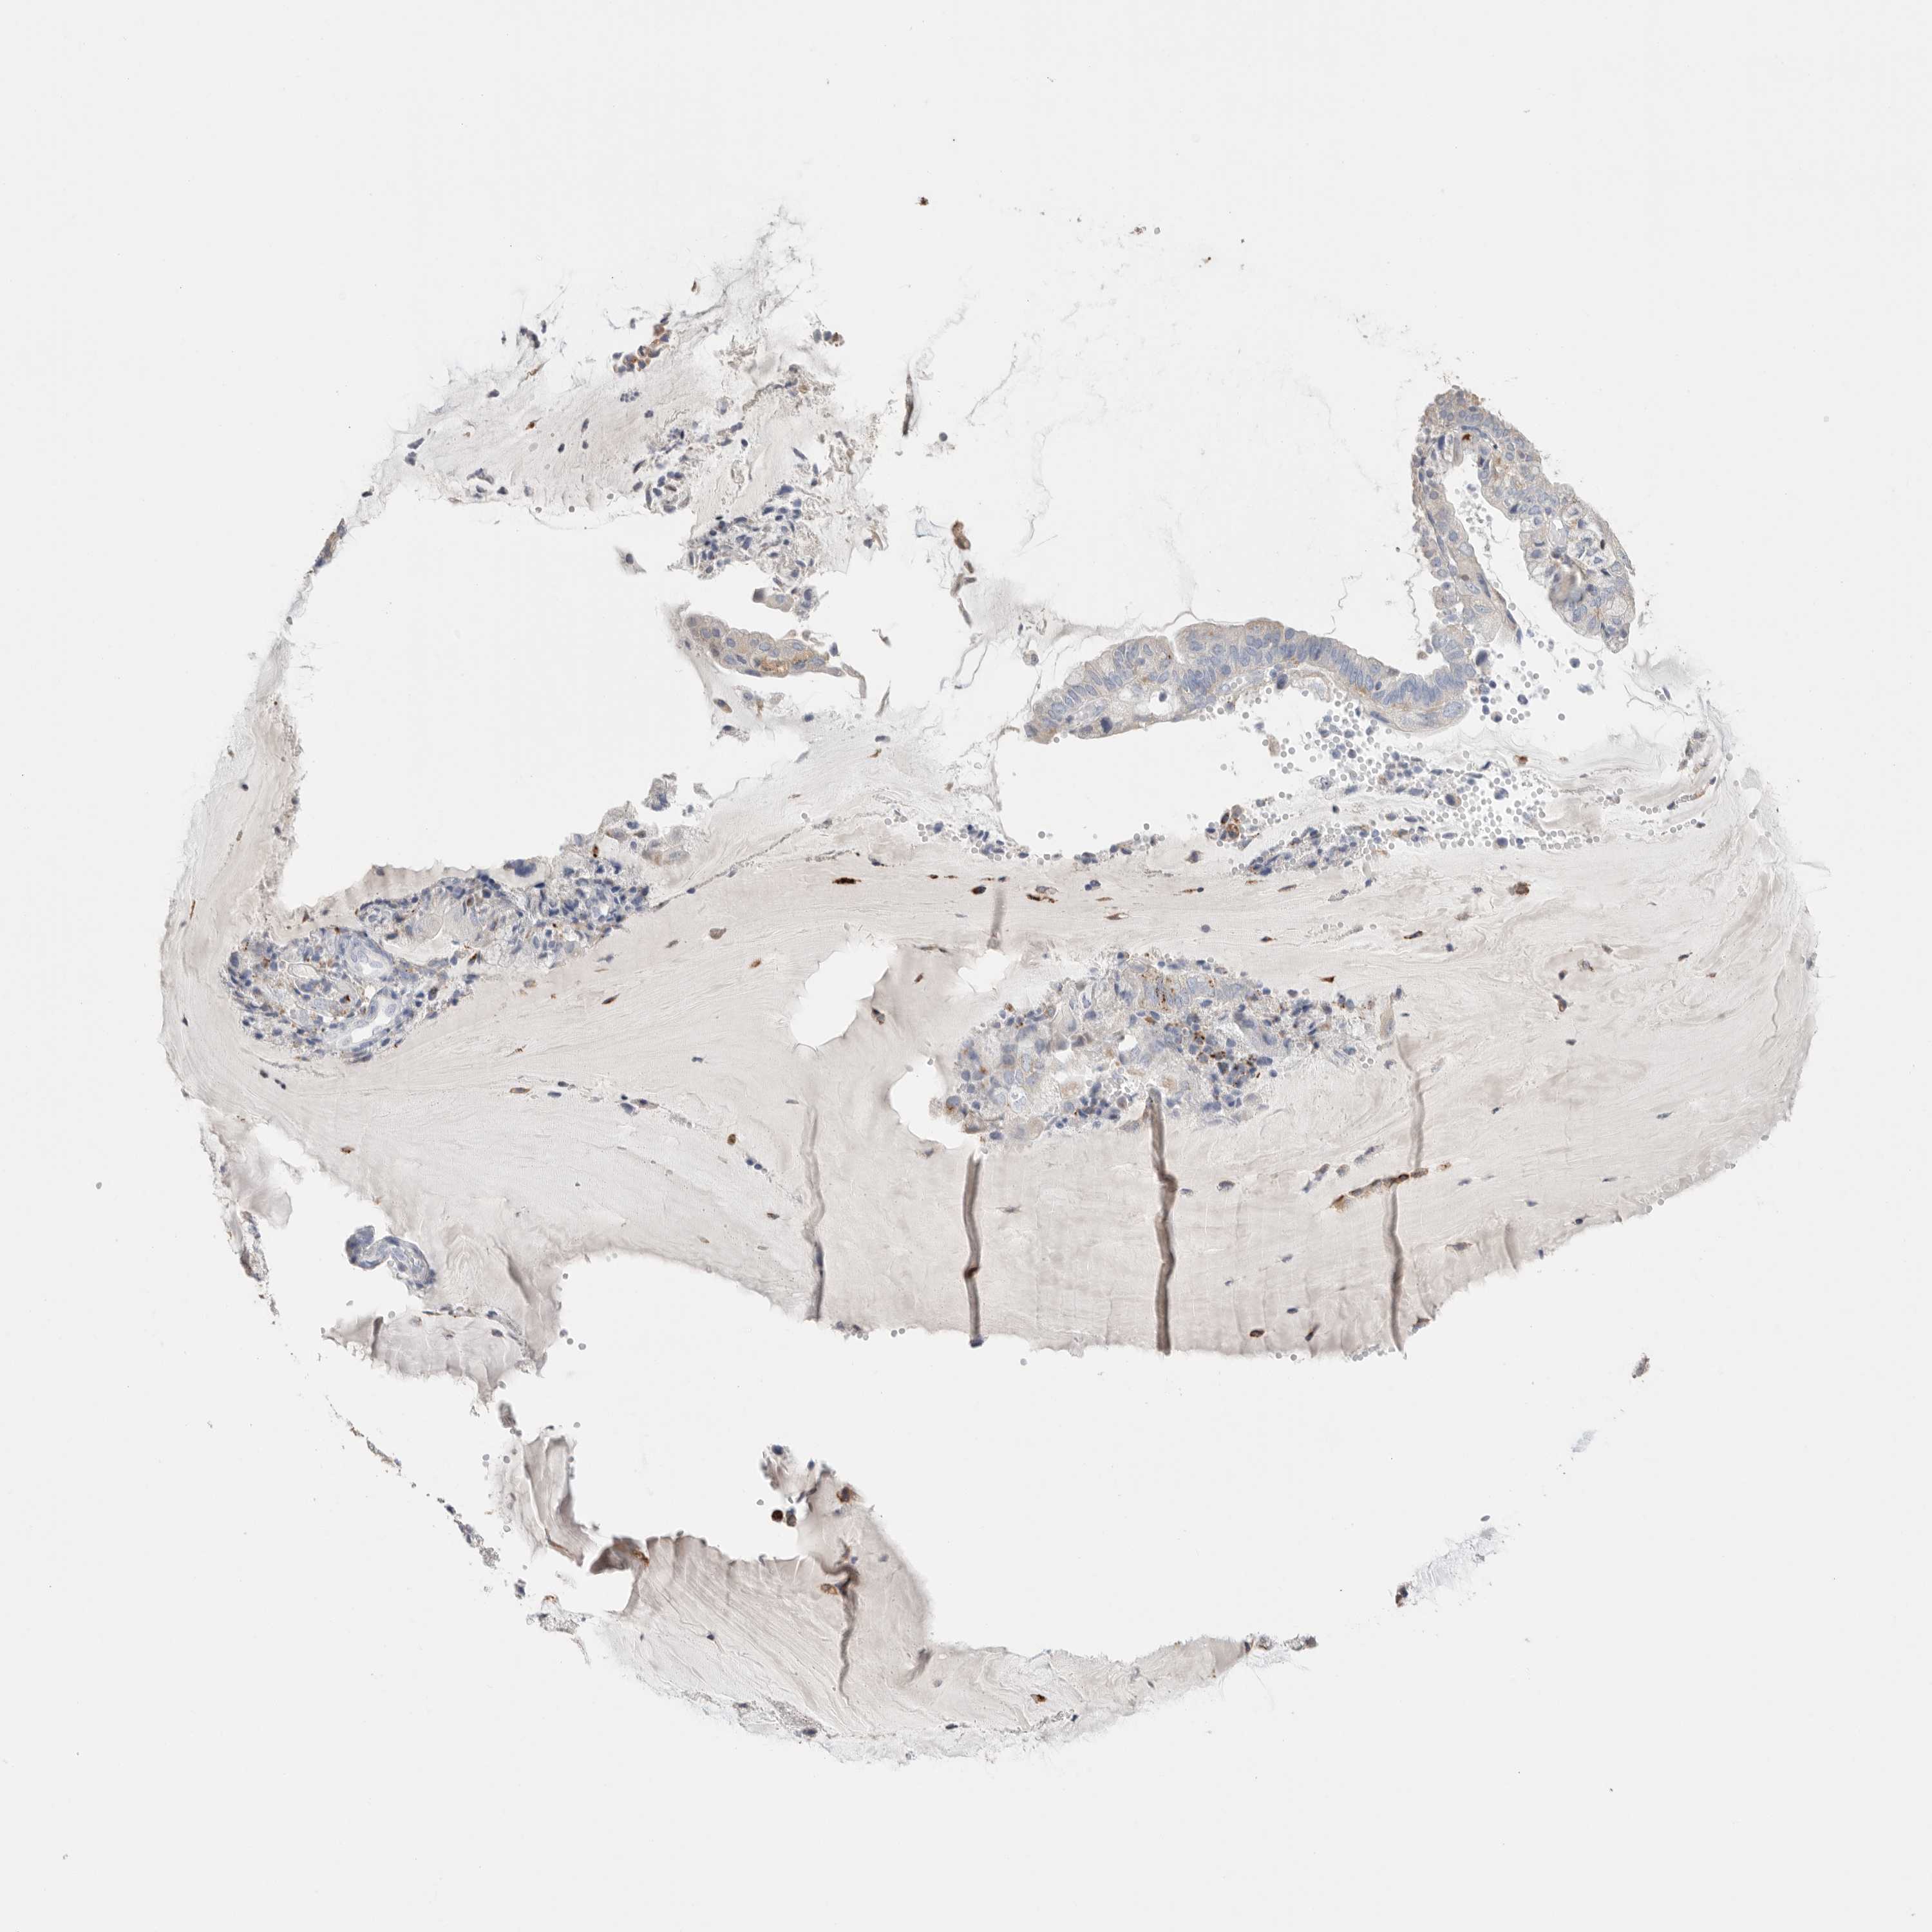

ENDOMETRIAL CANCER - Protein expressioni

A mouse-over function shows sample information and annotation data. Click on an image to view it in a full screen mode. Samples can be filtered based on level of antibody staining by selecting one or several of the following categories: high, medium, low and not detected. The assay and annotation is described here.

Note that samples used for immunohistochemistry by the Human Protein Atlas do not correspond to samples in the TCGA dataset.

Antibody stainingi

Antibody staining in the annotated cell types in the current human tissue is reported as not detected, low, medium, or high, based on conventional immunohistochemistry profiling in selected tissues. This score is based on the combination of the staining intensity and fraction of stained cells.

Each image is clickable and will lead to virtual microscopy that enables deeper exploration of all samples and also displays staining intensity scores, fraction scores and subcellular localization as well as patient and tissue information for each sample.

Antibody HPA025226

Antibody CAB019296

Staining

High

Medium

Low

Not detected

Intensity

Strong

Moderate

Weak

Negative

Quantity

>75%

75%-25%

<25%

None

Location

Nuclear

Cytoplasmic/membranous

Cytoplasmic/membranous,nuclear

Adenocarcinoma, NOS

Adenocarcinoma, metastatic, NOS